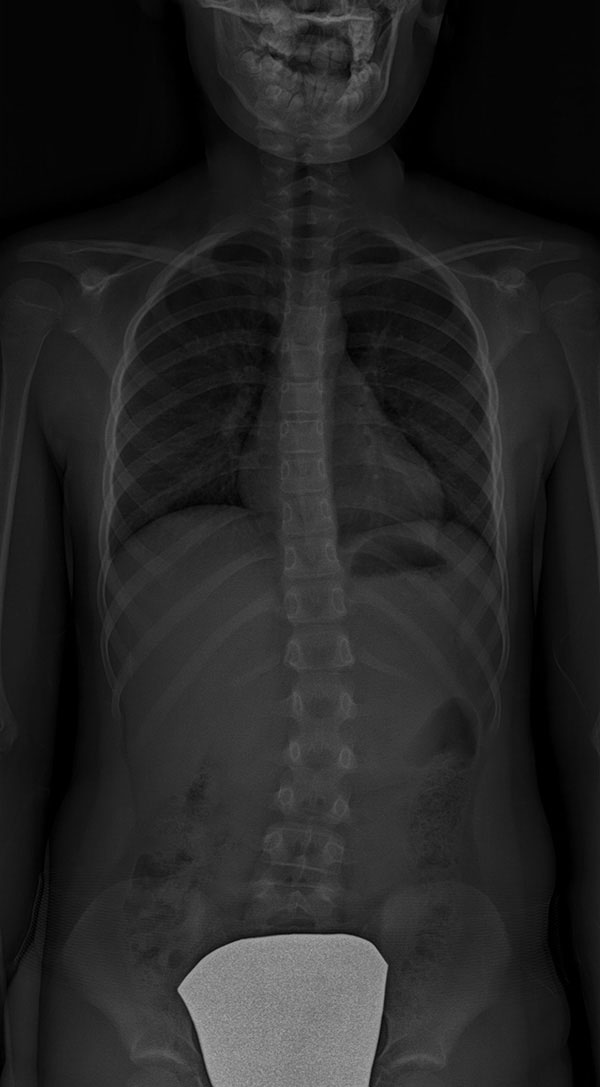

Scoliose thoraco-lombaire (dorso-lombaire) – située dans la colonne vertébrale entre la région thoracique et le bas du dos.

![]() |